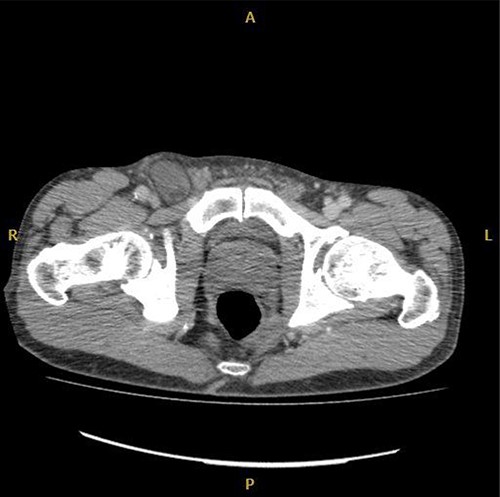

Computed tomography (CT) was reported as demonstrating an inguinal hernia containing fat and possibly the vermiform appendix (Figs 1 and 2). There was no conclusive evidence of appendicitis.